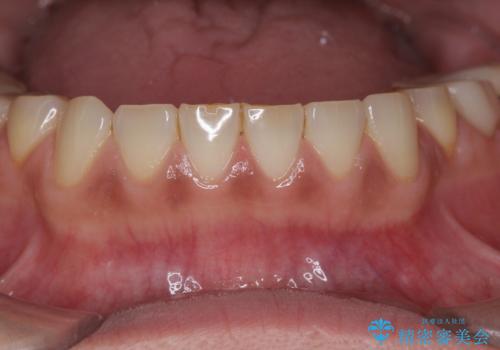

- 歯ぎしり・嘔吐症により歯がすり減ってしまい、色調・見た目を改善したいと来院されました。

神経を温存したまま仮歯に置き換え、噛み合わせの安定を確認したのちに すり減りに強いジルコニアクラウンで最終的な仕上げを行います。

歯の形態・色調を大きく変更する場合ジルコニアクラウンによる治療が耐摩耗性・審美性の観点から推奨されます。